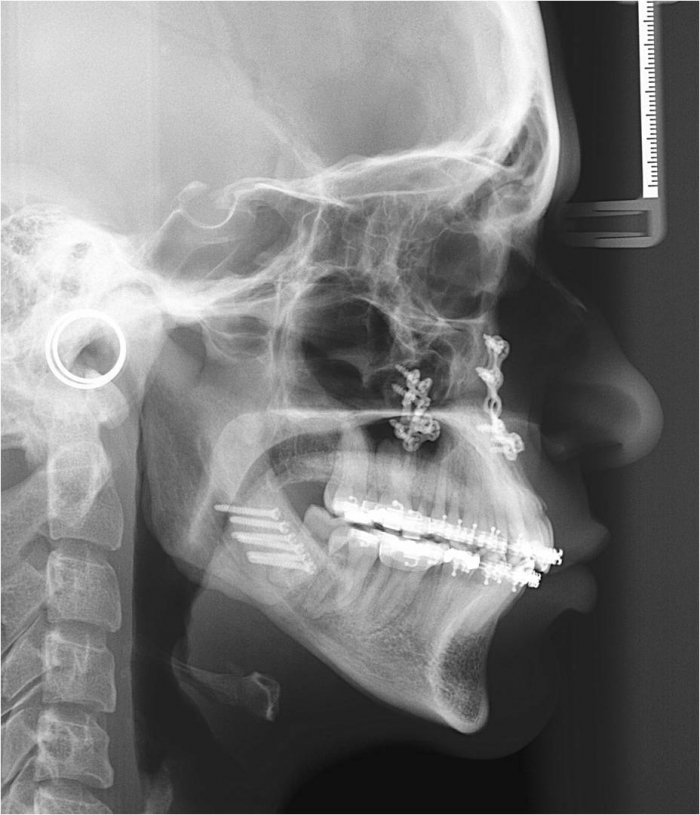

Telerradiografia inicial